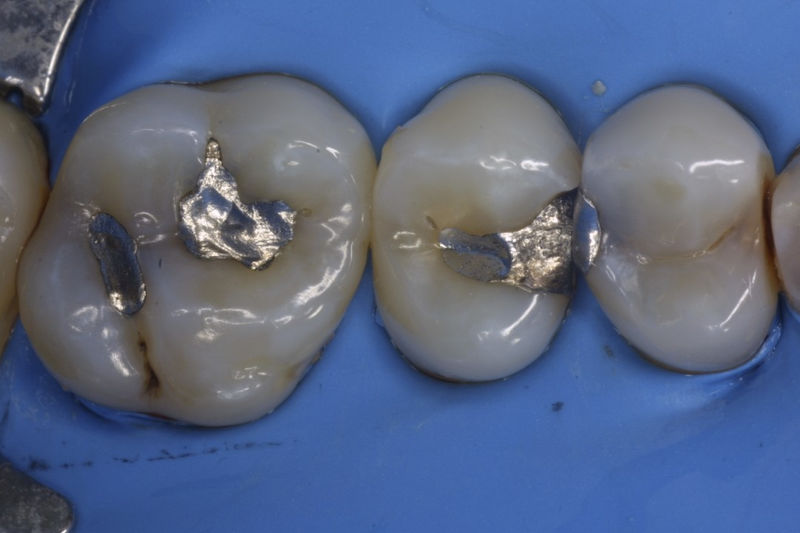

Disciplina fundamental de la Odontología enfocada en el diagnóstico, prevención y tratamiento restaurador de las piezas dentales que han sufrido daños. Su objetivo principal es devolver al diente su equilibrio biológico, funcional y estético cuando su integridad ha sido alterada. Resinas directas, incrustaciones, coronas.

Restauraciones fabricadas en el laboratorio con materiales estéticos, los cuales cubren de manera parcial dientes posteriores. Se utilizan primariamente para restaurar dientes con caries, fracturas y/o defectos amplios. Para poder enviar el caso al laboratorio se toman impresiones utilizando materiales de impresión o técnicas modernas digitales.

Implante fracasado, extracción, carillas, coronas y prótesis fija.